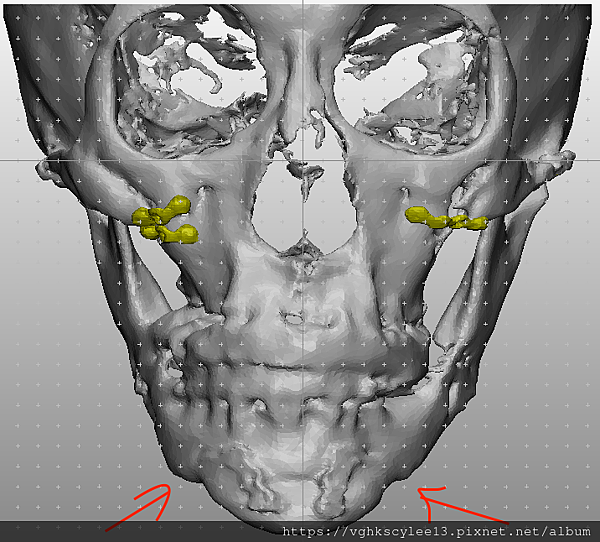

下圖:不對稱下巴骨架,透過列印技術可以做出調整下巴歪斜的假體組合。

歪斜下巴調整性假體設計

下圖範例:歪斜不對稱下巴經3D導航客製化導航矯正性假體

(下圖)3D模擬後工程師版的設計下巴假體的外型。

經過李醫師醫師對客戶外型的判斷,修改工程師的設計,建議更改後的假體模型(下圖)

(上圖)經過李醫師醫師對客戶外型的判斷,修改工程師的設計,建議更改後的假體模型。所以嘍,醫師的美感與專業度必須要做判斷,3D列印只是精準工具但是必須有專業醫師的判斷才可以完美!

下圖: 在李醫師確認後完美精準例印

窄小後縮的下巴,以精準3D列印技術來客製化醫師判斷後的外型下巴假體,一起改善嘴形相對的狀態。

窄小後縮的下巴,以精準3D列印技術來客製化醫師判斷後的外型下巴假體,一起改善嘴形相對的狀態。

3D模擬後 列印出吻合的設計下巴假體